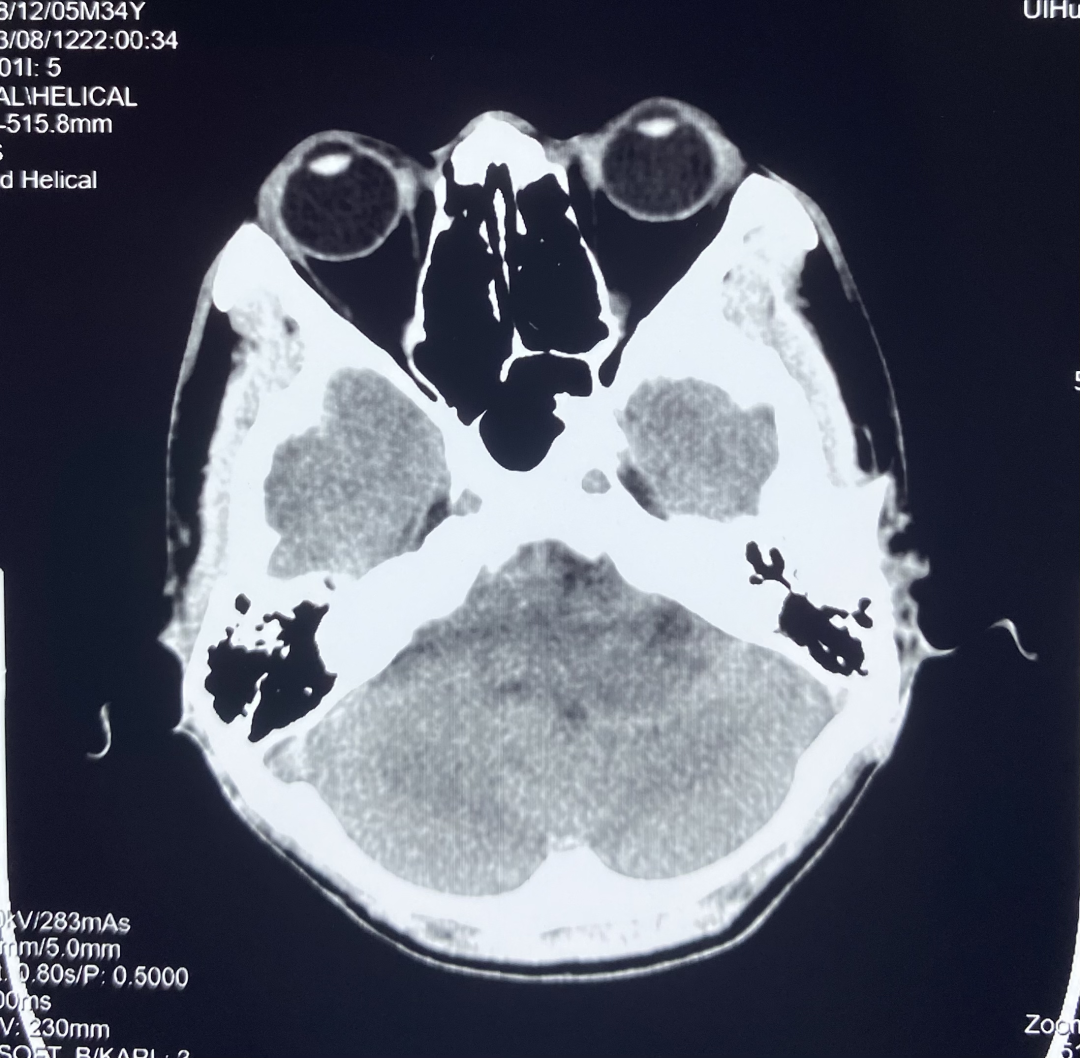

1、颅脑 CT 平扫

颅脑 CT 平扫显示左侧桥小脑角区可见团块状异常密度,大小约 3.0*3.4 cm,边界不清,内部密度欠均匀,可见低密度坏死区,左侧内听道较对侧扩大,邻近小脑受压。

诊断:左侧桥小脑角区占位,建议进一步检查。